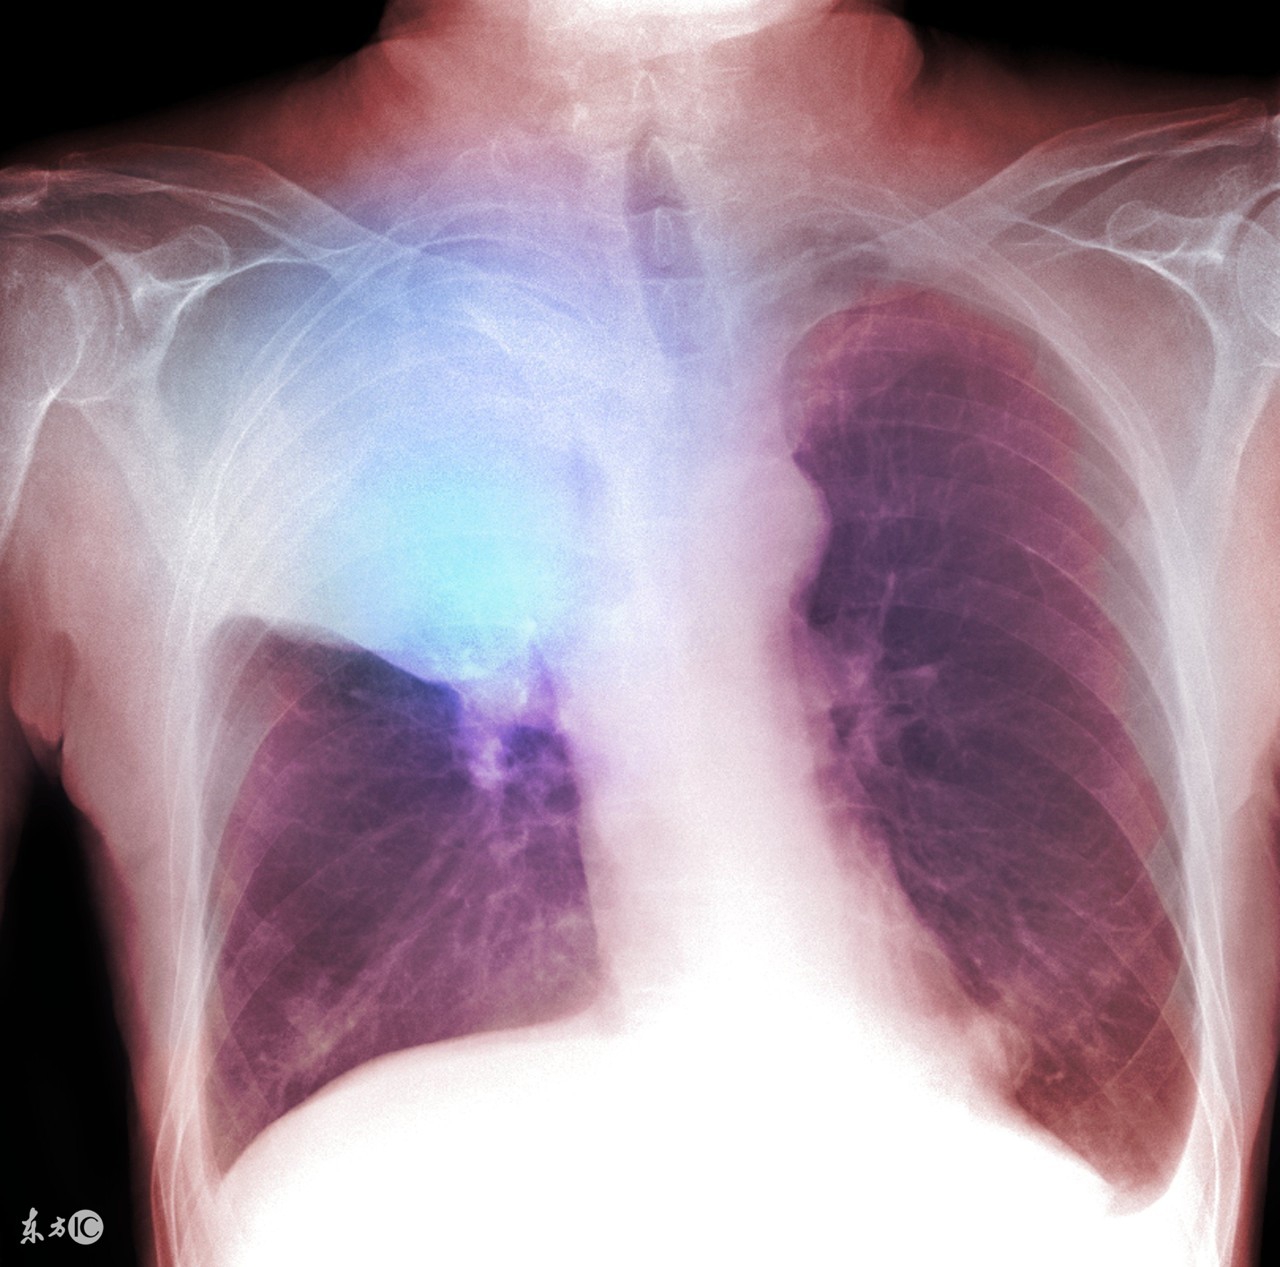

肺癌发热不能小看

相针对其他癌症而且,肺癌的发热原因可以明确到以下两点:

肿瘤逐渐增大阻塞支气管就会出现阻塞性肺炎,这就是炎症引起的发热,如果通过抗生素治疗是可以控制体温的,但如果不彻底解决阻塞支气管的肿瘤,就会复发;

2.再有就是所谓的癌性热,癌性热一般是以低烧的情势出现的,也就是温度低于38.5℃。虽然能通过物理降温的方式控制低烧,但这类的发热一定要通过对癌症根本性的治疗才能得到有效控制。